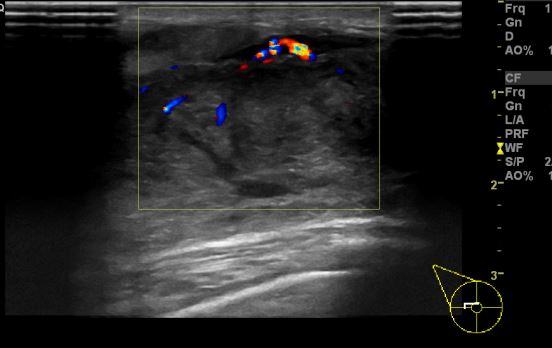

상기환자 좌측 유방에 만져지는 멍울로 내원하신 70대 여성분으로 좌측 만져지는

멍울 조직검사 시행하여  암 진단 되었습니다.